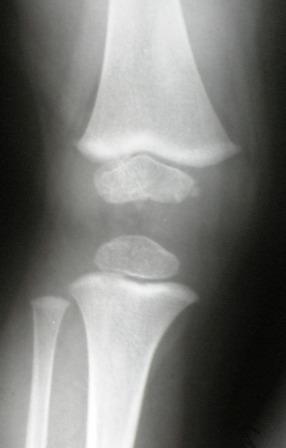

Родился и рос нормальным ребенком. Последнее время стал жаловаться на ножки. Мама заметила Х-образную деформацию нижних конечностей. При осмотре отмечена легкая вальгусная деформация коленных суставов, плоскостопие. Предполагаю, что это МЭД - множественная эпифизарная дисплазия. Р-грамма прилагается. Какие варианты лечения?.